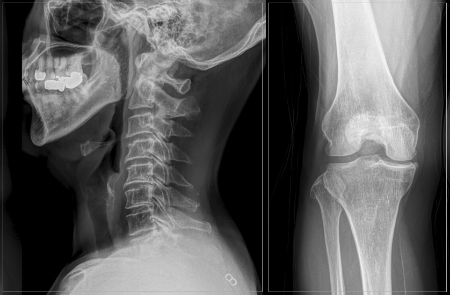

척추관협착증은 척주관이 좁아지면서 신경을 압박하는 질환이다. 주요 원인은 노화로 50~60대 이후 나이가 들수록 발병률이 증가한다. 척추관협착증은 '허리' 문제이지만 신경이 내려가는 '다리'에 증상이 두드러진다. 특히, 가만히 있으면 증상이 없고 서 있거나 걸을 때 통증과 저림 증상이 나타나는데, 이런 이유로 무릎 등 다리 문제로 착각하는 경우가 많다. 심한 경우는 10분 이상 걷기 힘들어하는 등 보행 장애로 일상생활에 큰 불편을 호소하기도 한다.

특히, 척추관협착증은 무릎 연골이 닳아 염증이 생기는 무릎 퇴행성 관절염과 헷갈리기 쉽다. 무릎이 망가지면 걸음걸이가 바르지 못하고 걷다 서기를 반복하는데, 이 과정에 척추 건강이 나빠지며 증상이 악화하는 악순환이 반복된다. 통증을 줄이기 위해 자세가 틀어지거나 양반다리, 짝다리 등을 자주 취해도 골반 불균형을 초래할 수 있다. 체형 변형은 물론 허리디스크, 척추측만, 고관절 통증의 '씨앗'이 될 수 있다는 의미다.

보행장애가 심할 때 두 질환을 구분하는 방법의 하나는 허리를 굽혀보는 것이다. 척추관협착증은 허리를 펼 때 통증이 심해지고 허리를 앞으로 숙이면 통증이 완화하는 특징이 있다. 반면 무릎 퇴행성 관절염은 척추관협착증과 달리 저림 증상보다는 무릎을 움직일 때 통증이 나타나는 특징이 있다. 또 관절염이 진행될 때 무릎에 부종이 많이 발생하고, 이때 뻣뻣한 느낌 등이 동반된다. 무릎과 허리는 어느 곳에 증상이 먼저 나타났느냐와 관계없이 문제가 있다면 전부 치료하는 게 좋다. 한쪽에서 발생한 문제가 통증으로 인한 자세 변화, 체중 부하를 유발해 다른 쪽의 문제를 더 악화시킬 수 있기 때문이다.

실제 목디스크 환자는 직접적인 목 통증보다 어깨나 팔 등 다른 곳에서 증상이 시작되는 사례가 많다. 목덜미나 어깨 위쪽의 통증이 가장 흔하고 팔과 어깨 저림, 손가락 끝까지 저림이 타고 내려오는 증상이 나타나기도 한다. 심한 경우 척수 손상으로 다리의 힘이 약해지거나 마비가 발생하기도 한다.